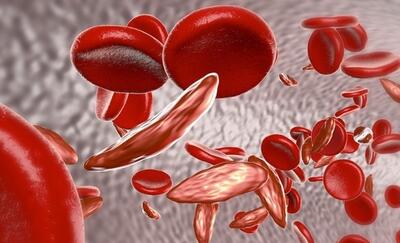

لخته شدن خون معمولا در کدام عضو بدن رخ می دهد؟ - خبرنامه

لخته شدن خون، یا ترومبوز، بخطرات جدی برای سلامتی دارد. عدم تحرک طولانی مدت، ضربه، اختلالات پزشکی و عوامل هورمونی از عوامل کلیدی هستند. افراد قد بلندتر به دلیل